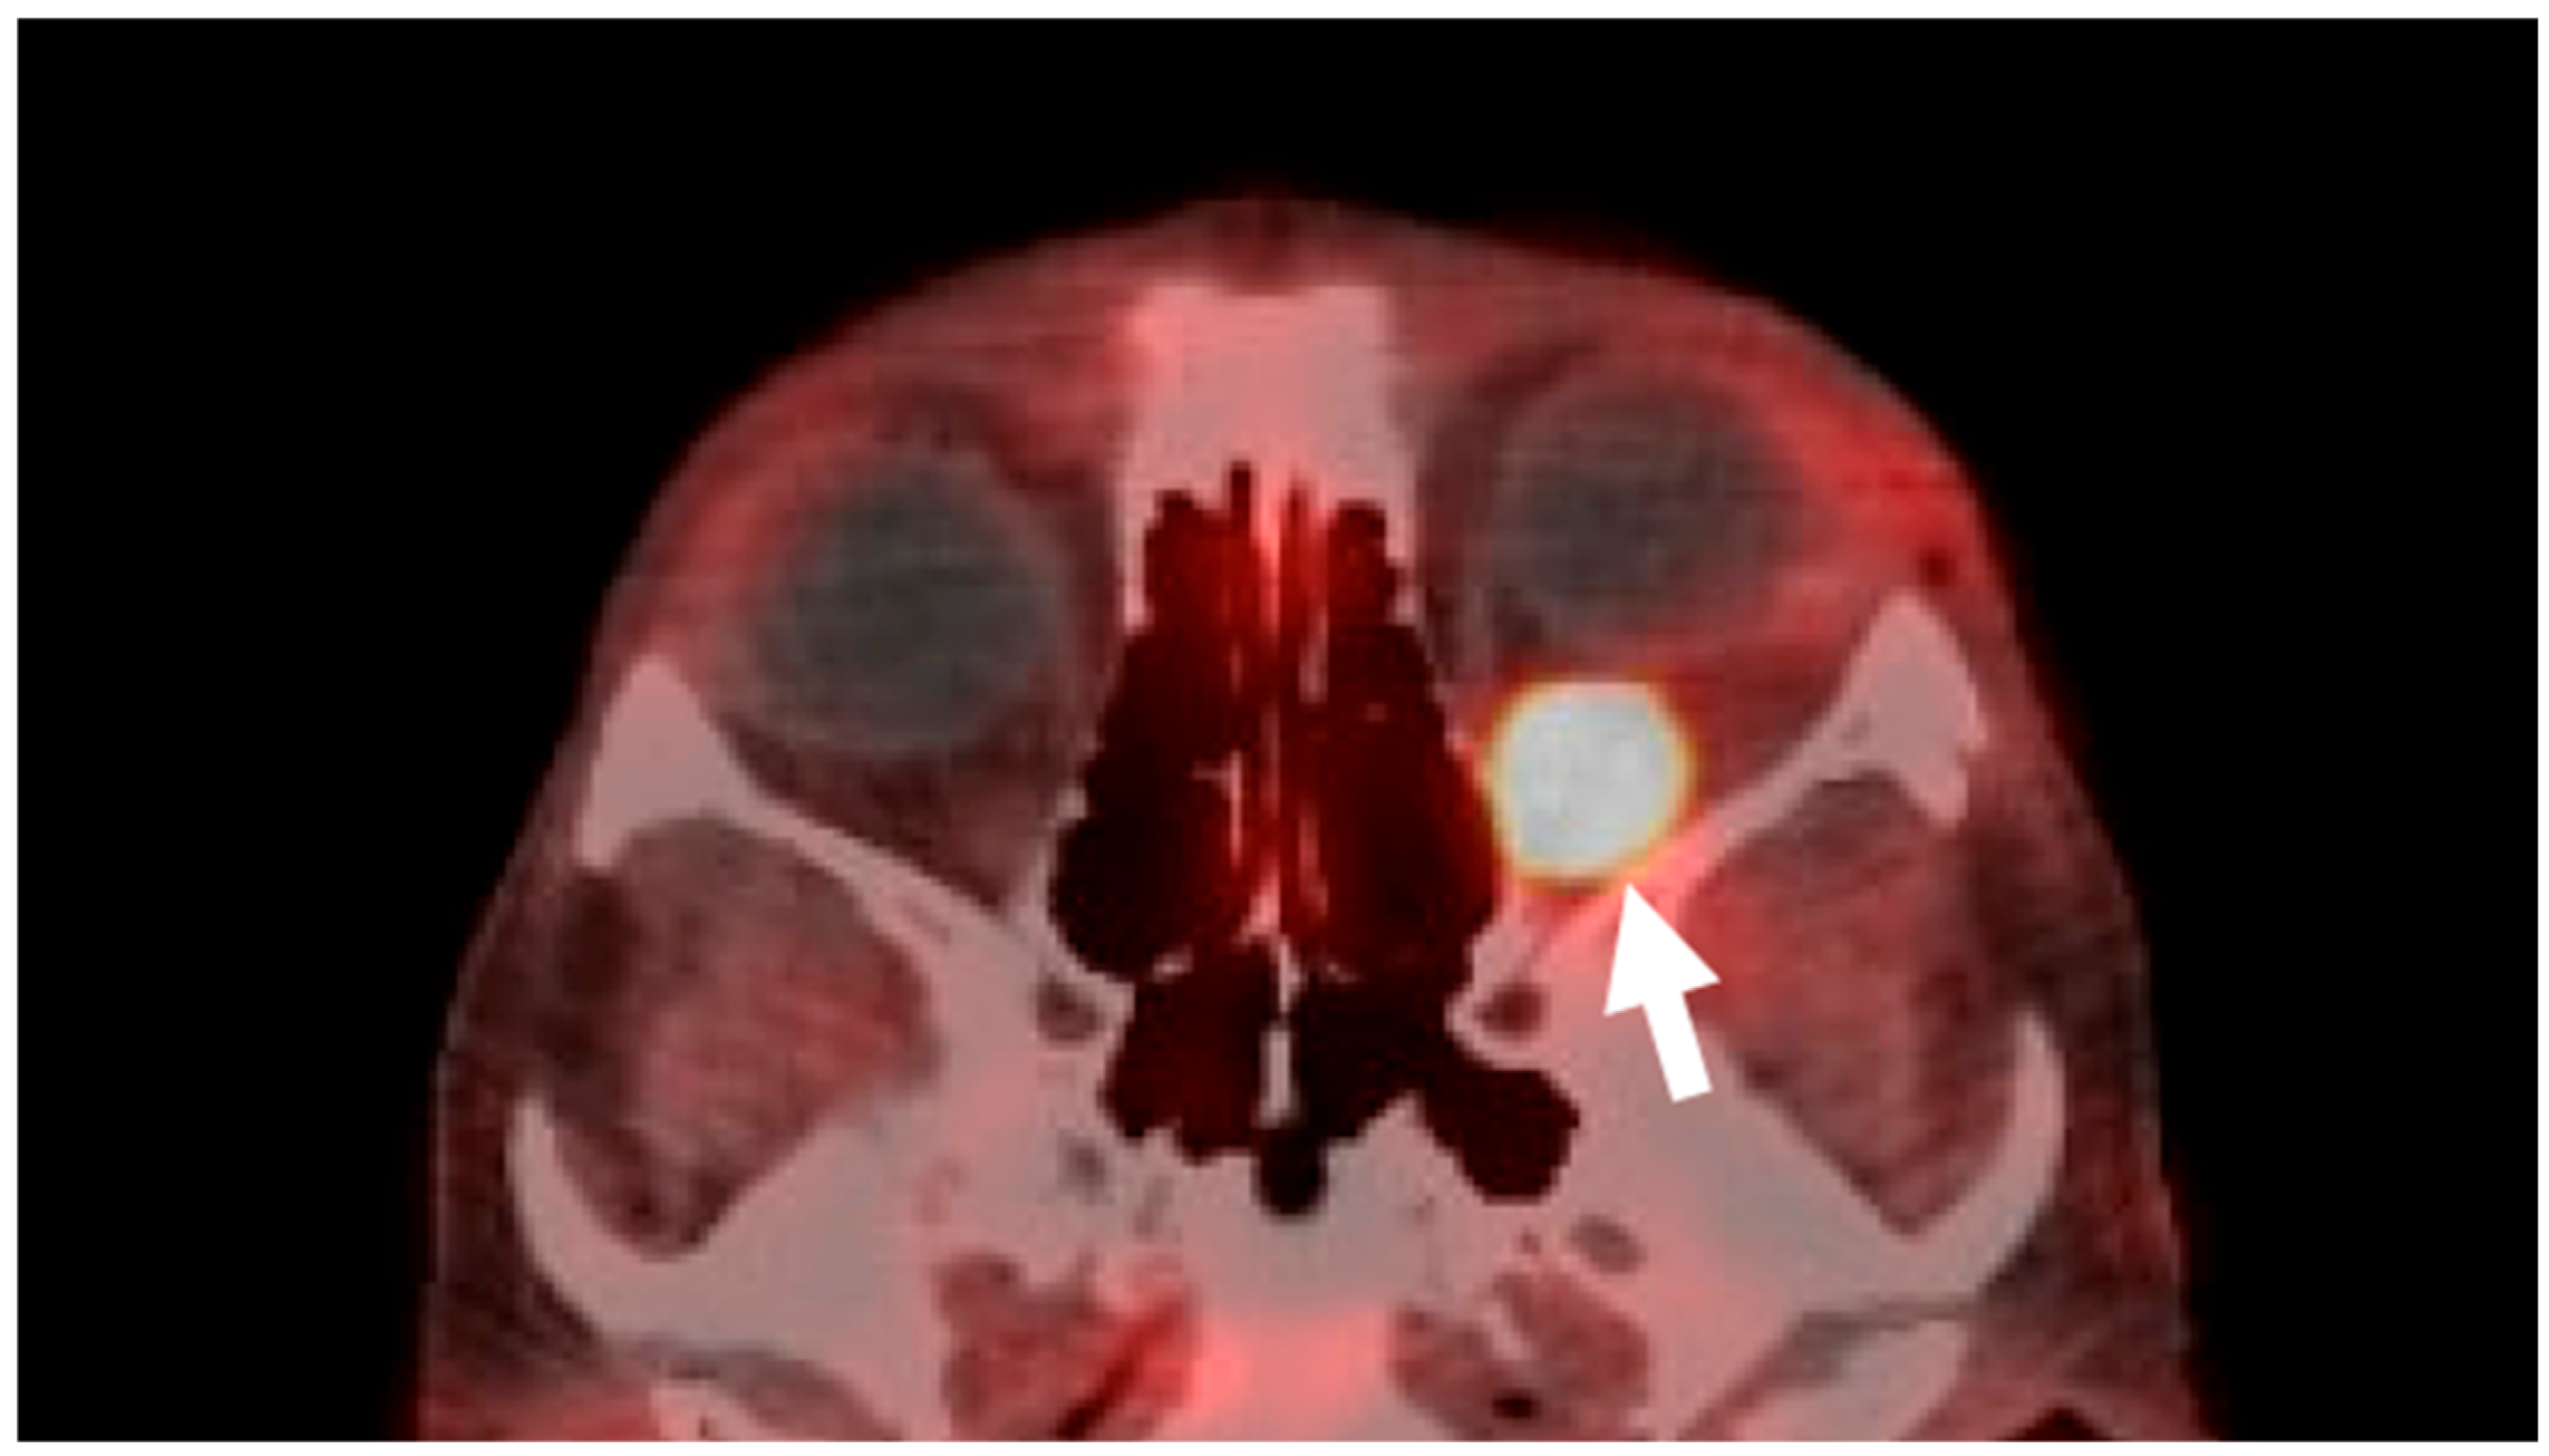

2. Case Presentation